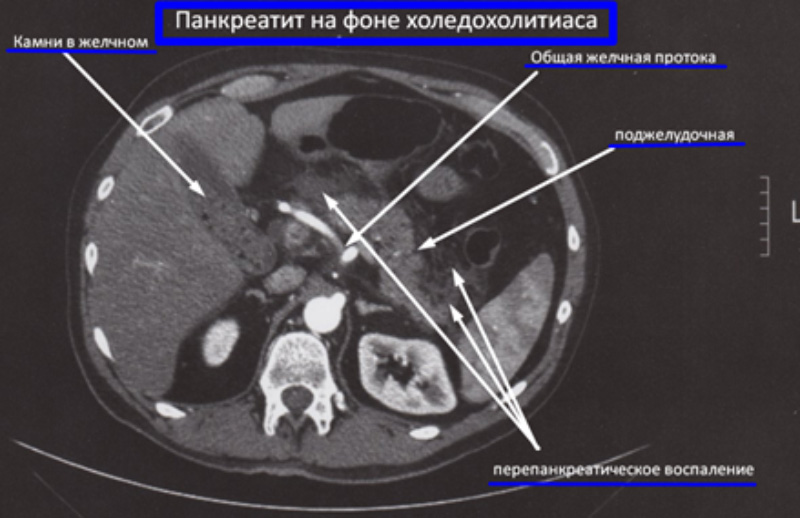

Камни в желчном пузыре. Желчные камни мигрируют из желчного пузыря, что может привести к обтурации сфинктера Одди (см статью «ХИРУРГИЯ: Холецистит (Краткий обзор)»)

Панкреатит на фоне холедохолитиаза